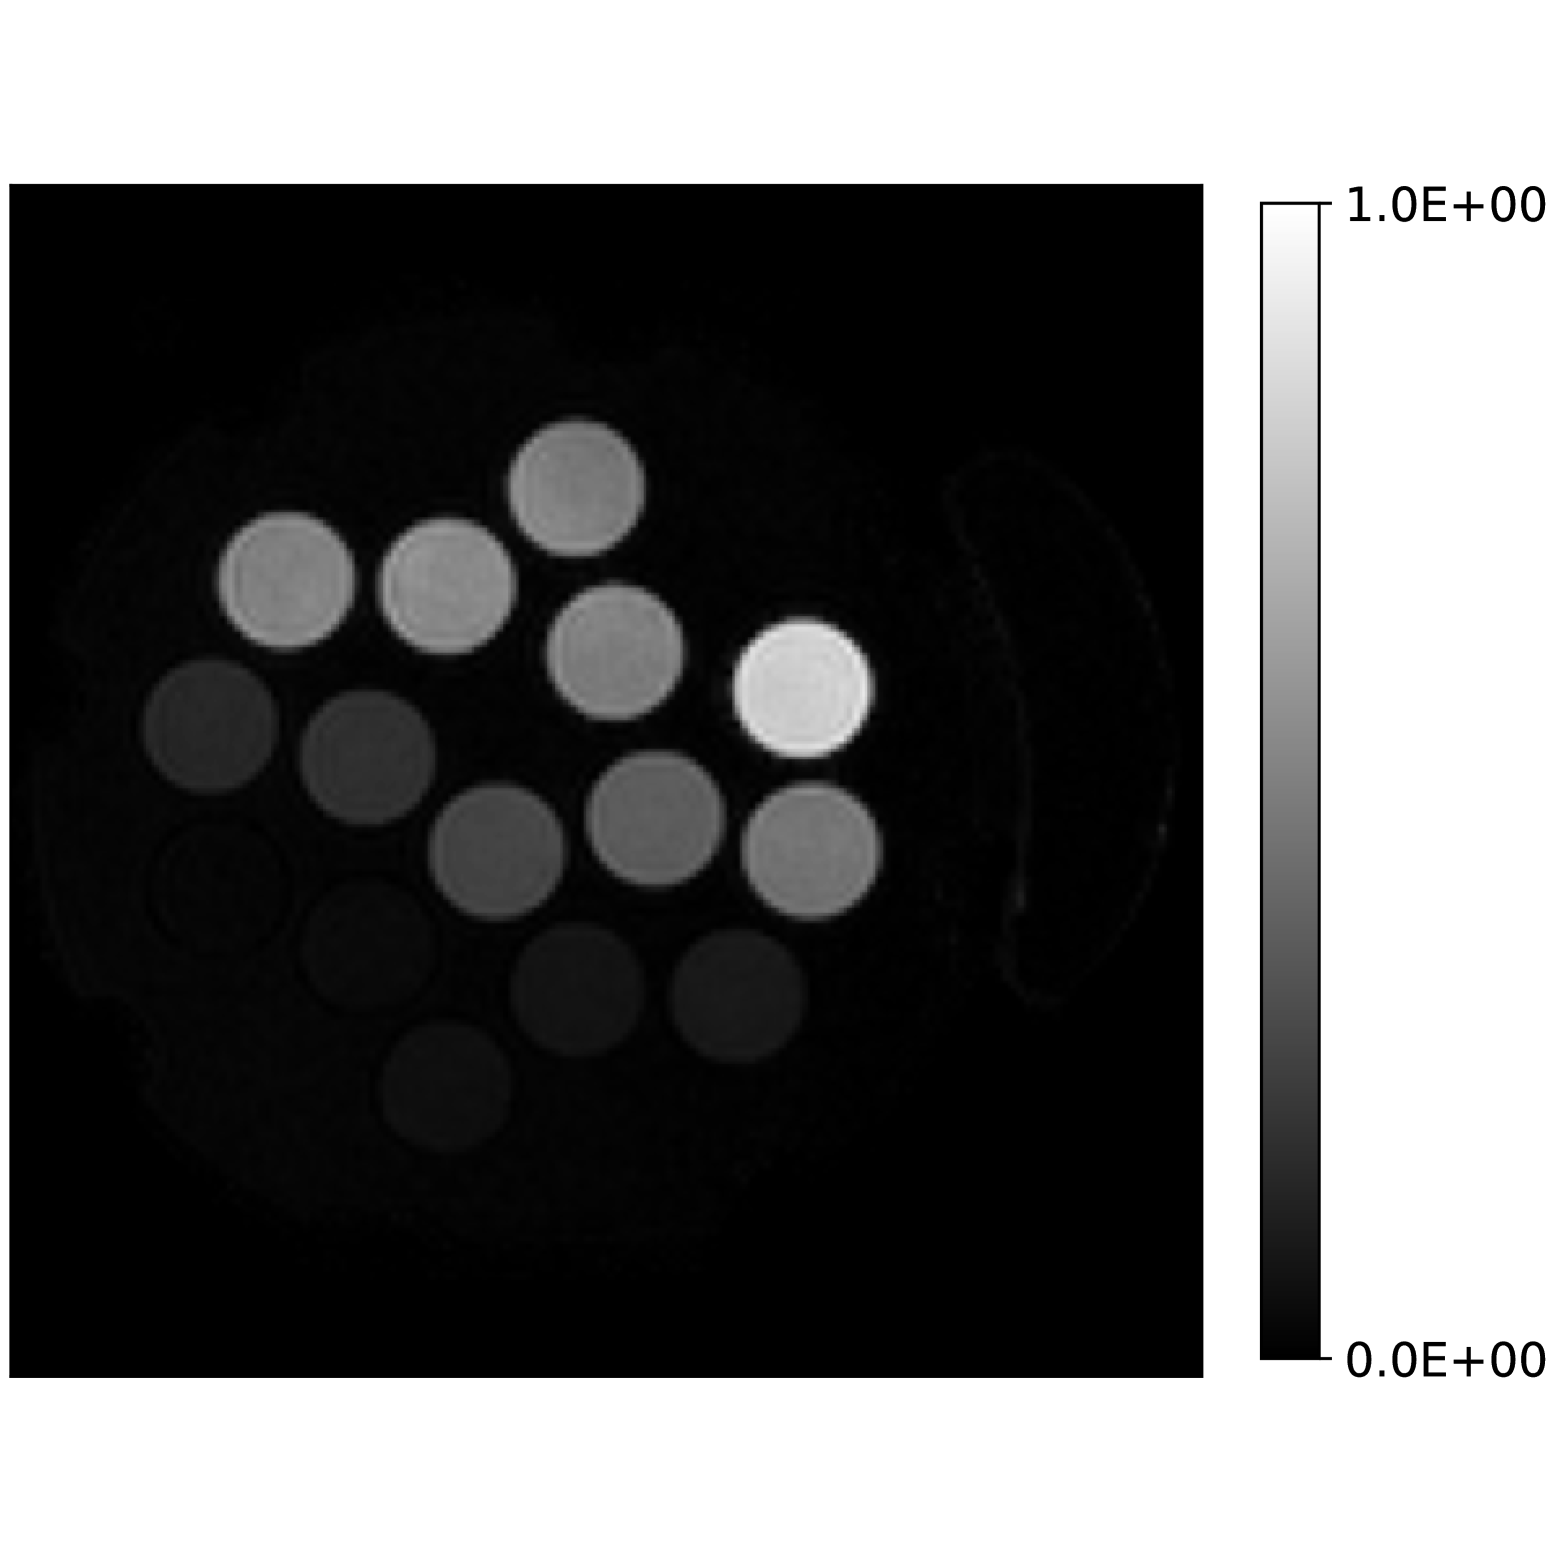

Our theoretical results show that generic concentrations and maps can be recovered exactly even when the fieldmap is not identifiable. To illustrate the impact of this fact, we perform a recovery experiment on a water (Fig. 2(a)), fat (Fig. 2(b)) and silicone (Fig. 2(c)) in silico phantom. The concentrations are all real. The values for the fieldmap and used to generate the signal are shown in Figs. 2(d) and 2(e). The echo times have the form where ms and ms with .

In Figs. 2(f), 2(g) and 2(h) show the recovered concentrations of water, fat and silicone, and Fig. 2(j) shows the recovered . These recovered quantities are all qualitatively similar to their true values. In contrast, Fig. 2(i) shows the recovered fieldmap, which differs from its true value. By comparing the errors in the recovered concentrations, we see that they are within a reasonable accuracy except in regions with a large magnitude for the fieldmap gradient, indicating a bound that is too small (Figs. 2(k), 2(l) and 2(m)). A similar behavior is seen in the recovered (Fig. 2(o)). The error for the recovered fieldmap tends to be larger outside the area of the phantom (Fig. 2(n)).